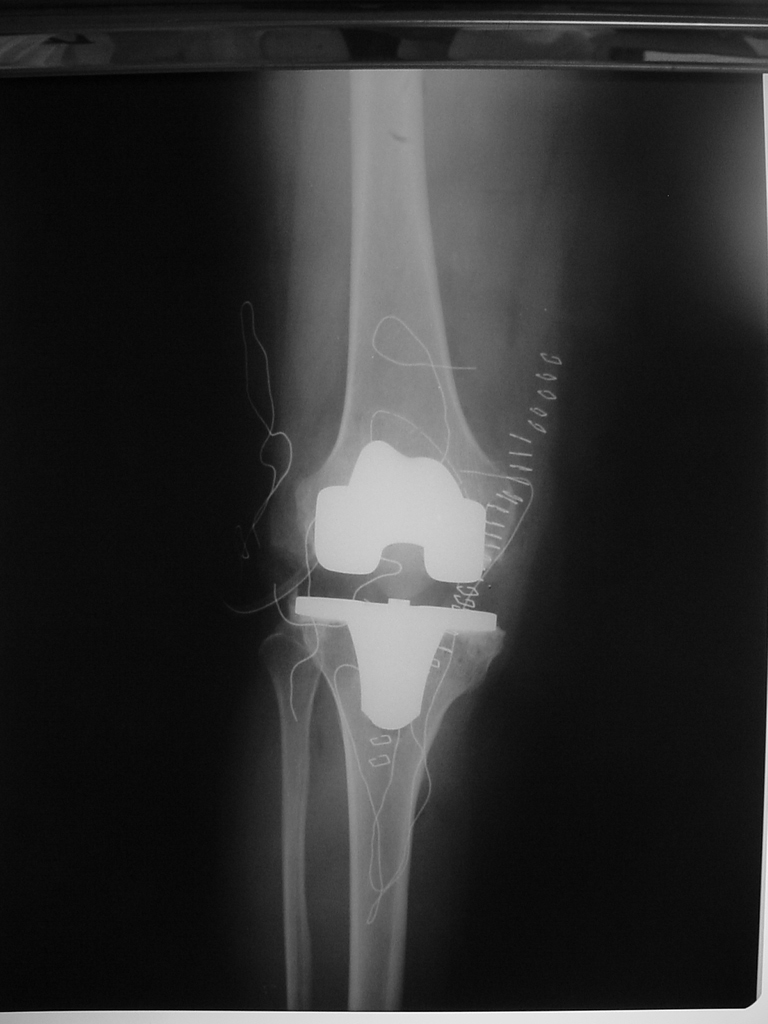

Total Diz Protez ameliyatı kliniğimizde endikasyon dahiline her yaşa başarı ile uygulanmaktadır. Örnek olgumuz: